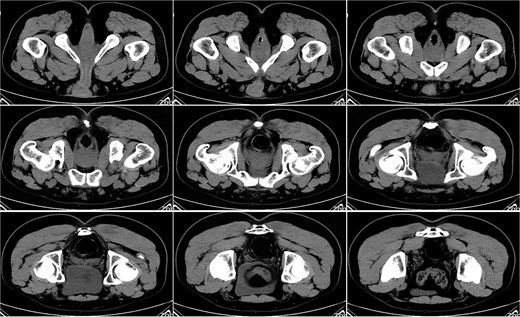

On postoperative Day 15, a complete blood count showed a white blood cell count of 9.12 × 109/l and a neutrophil percentage of 77.5%. Pelvic CT demonstrated rectal wall edema, anterior wall perforation, and partial absorption of the surrounding infection, indicating reduced infection severity compared to the previous scan on postoperative Day 10 (Fig. 3). Given the patient’s satisfactory response to antibiotic therapy and absence of ongoing infection signs, intravenous antibiotic treatment was discontinued.